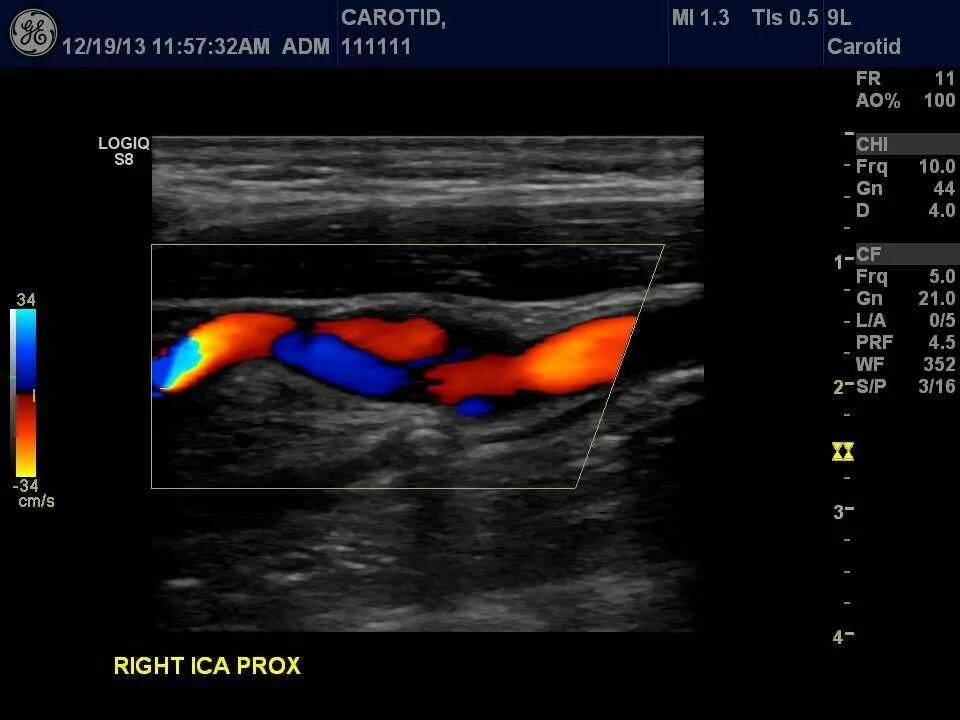

Что такое дуплексное сканирование головы